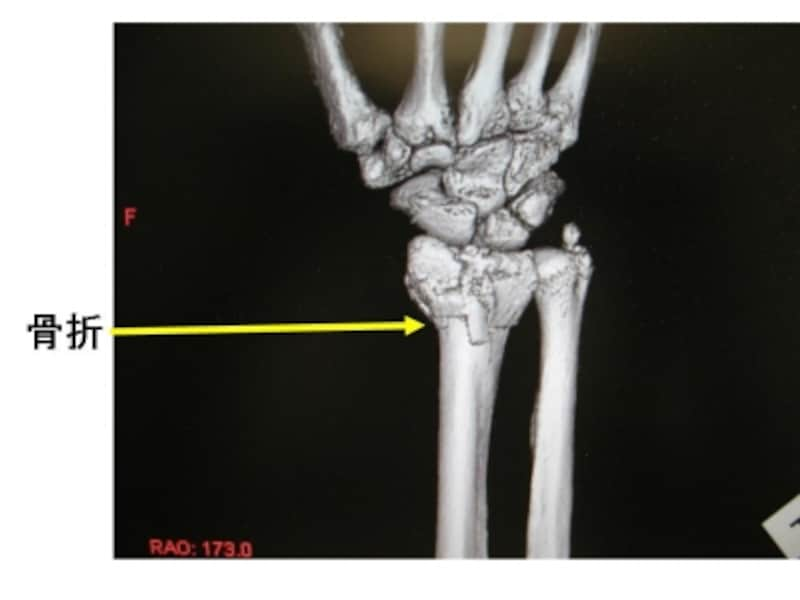

手関節部3次元CT像。

断層写真から計算で、3次元画像を作成できます。